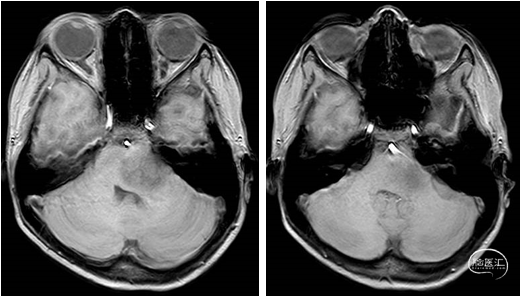

2023年9月13日 MRI+C